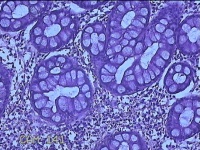

乙状结肠粘膜

性别

男

年龄

52岁

临床诊断

结肠息肉

一般病史

乙状结肠可见息肉

标本名称

大体所见

灰白粉红色组织小米大一团。

图1

自动采图系统很方便,图片采太多没病变的图,几张就够了,而且制片技术急需改进,

有点增生性息肉的感觉